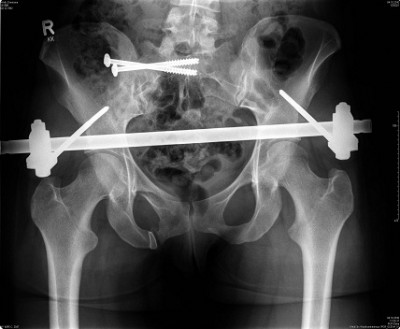

Ich kann zu dem Thema auch noch folgendes Bild beitragen:

Hm. Sechs Schrauben im Schlüsselbein. Und da soll mein Becken mit gerade mal vier Schrauben halten?